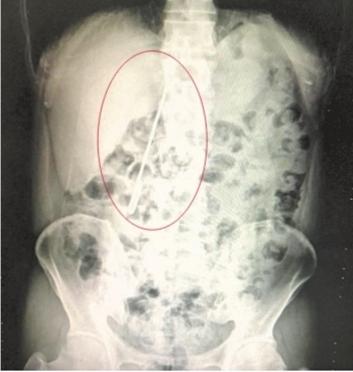

CT显示,毛衣针在常先生十二指肠拐弯处已穿透肠壁,尖端外露,有进一步损伤大血管及结肠的风险。医生立即为常先生实施手术,切开胃部取出毛衣针,并修补好十二指肠破口。